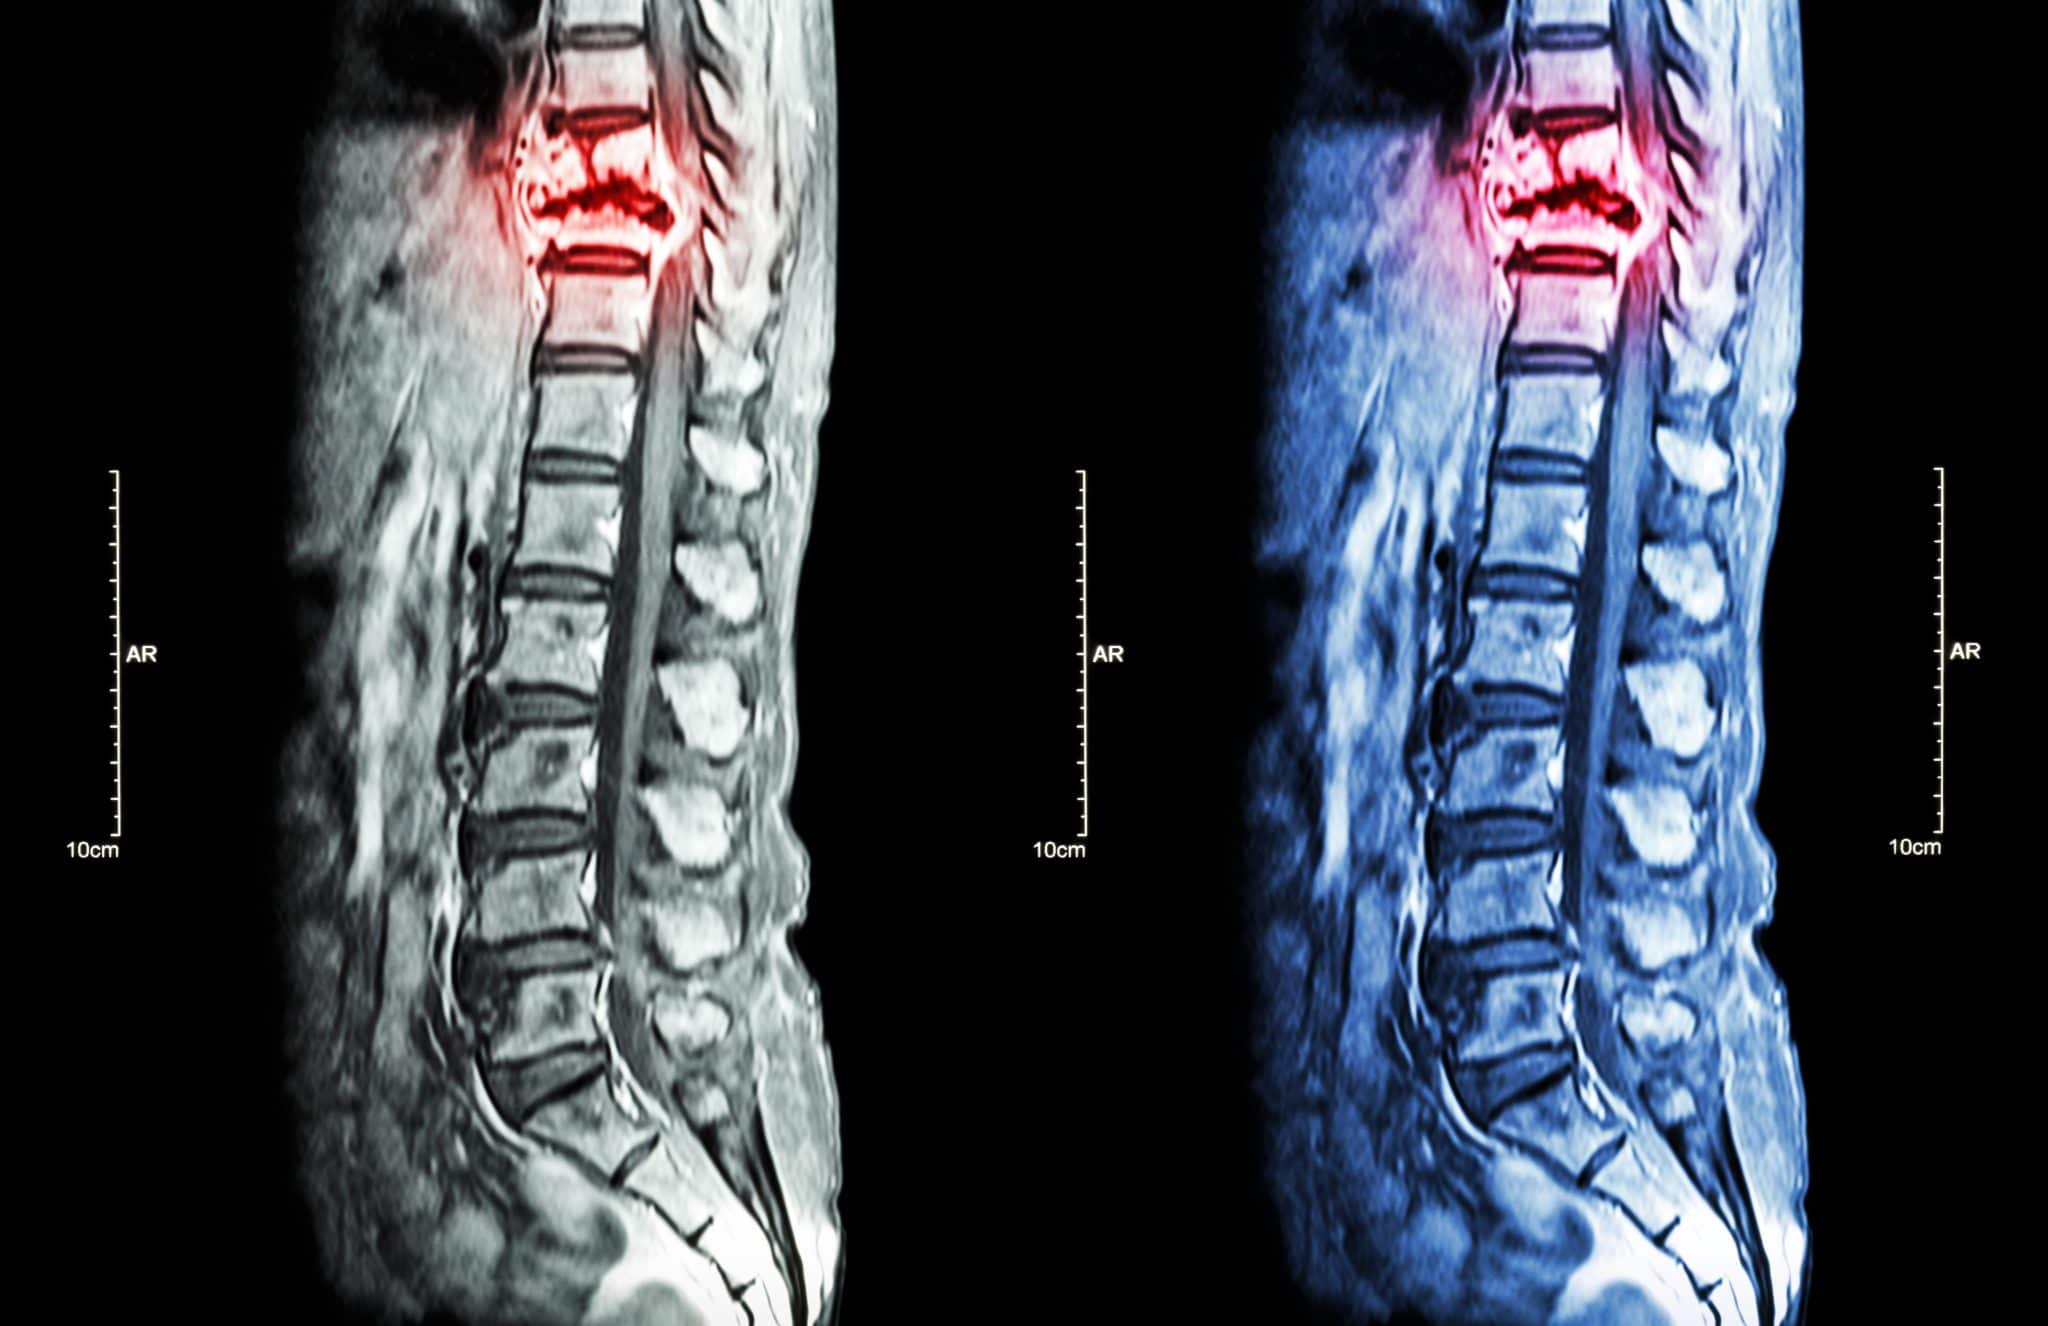

Long Term Nerve Damage Caused by Car Accidents

Spinal Cord Injuries, Neuropathy, and Car Accidents Philbrook Law Can A Car Accident Cause Neuropathy You can be fined up to £1,000 if you don’t tell dvla about a medical condition that affects your driving. Numbness and tingling in the feet or hands. You may be prosecuted if you’re. Peripheral nerves can be damaged in several ways: If you sustained your injury in an accident caused by. The main symptoms of peripheral neuropathy can include:. Can A Car Accident Cause Neuropathy.